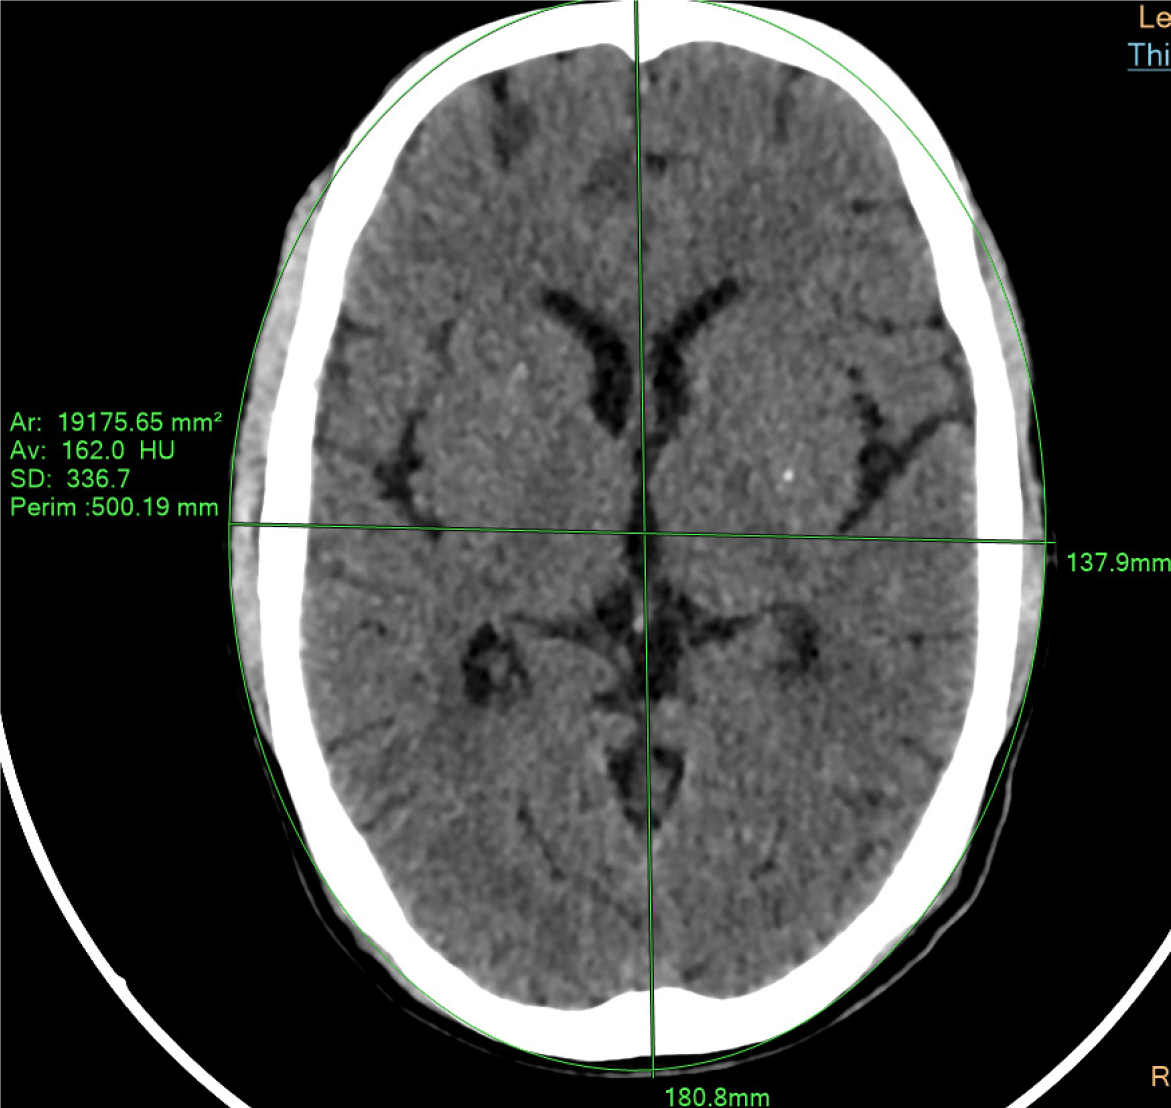

The AP length of the brain was measured along the Falx Cerebri, whereas the length of LAT was measured from right to left. using the measuring tools in CT post processing Techniques at the workstation extension, i.e., ruler and shape selector which can cover the entire head circumference and can measure the area under consideration (Figure 1).

The Deff was calculated using the AP and LAT dimensions of the diameter of brain using the formula as described in American Association of Physicist in Medicine (AAPM) report 204. Deff = (AP × LAT)1/2. It was unique for every patient as the measurements were different for AP and LAT diameters. The formula was used for manual calculation of dose.